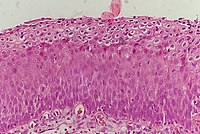

The earliest microscopic change corresponding to CIN is epithelial dysplasia, or surface lining, of the cervix, which is essentially undetectable by the woman. The majority of these changes occur at the squamocolumnar junction, or transformation zone, an area of unstable cervical epithelium that is prone to abnormal changes.[12] Cellular changes associated with HPV infection, such as koilocytes, are also commonly seen in CIN. While infection with HPV is needed for development of CIN, most women with HPV infection do not develop high-grade intraepithelial lesions or cancer. HPV is not alone enough causative.[13]

It most commonly occurs at the squamocolumnar junction of the cervix, a transitional area between the squamous epithelium of the vagina and the columnar epithelium of the endocervix.[12] It can also occur in vaginal walls and vulvar epithelium.

CIN is classified in grades:[17]

| Histology grade | Corresponding cytology | Description | Image |

|---|---|---|---|

| CIN 1 (Grade I) | Low-grade squamous intraepithelial lesion (LSIL) |

|